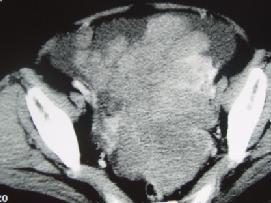

问题 50岁女性患者,消瘦乏力一年余,来院就诊,B超提示盆腔巨大包块,行CT检查如图所示,你认为最可能的答案是 ( )

选项 A、卵巢粘液瘤 B、卵巢皮样囊肿 C、卵巢囊肿 D、卵巢异位妊娠 E、卵巢癌

答案 E